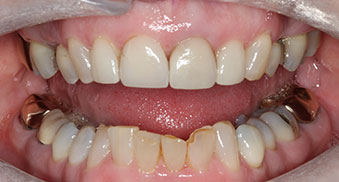

A 68-year-old woman came to our office with broken teeth and a damaged veneer. She wanted her teeth to look longer, whiter, and prevent further chipping.

A 68-year-old woman came to our office with broken teeth and a damaged veneer. She wanted her teeth to look longer, whiter, and prevent further chipping. She was also unhappy with the shape and colour of her front teeth. She had been experiencing bite issues, including jaw discomfort and tooth sensitivity, and had several previous failed dental treatments.

The patient was very happy with the results, both in terms of the comfort of her bite and the appearance of her teeth. By fixing her bite and making sure her teeth and jaw joint were in the correct position, we were able to create a functional and beautiful smile that met her expectations. Her risk for future dental issues was reduced, and she left our office feeling confident in her smile and oral health.